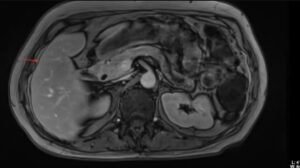

Ο εργαστηριακός έλεγχος ανέδειξε σημαντικά αυξημένα επίπεδα αγγειοδραστικού εντερικού πεπτιδίου (VIP), ενώ η απεικόνιση κατέδειξε όγκο στην ουρά του παγκρέατος με ηπατικές μεταστάσεις στα τμήματα VI, VII και III. Από το ατομικό αναμνηστικό αναφερόταν λαπαροσκοπική χολοκυστεκτομή.

Η ασθενής διαγνώστηκε με λειτουργικό νευροενδοκρινικό όγκο παγκρέατος (VIPoma) και υποβλήθηκε σε ρομποτική περιφερική παγκρεατεκτομή με σπληνεκτομή, σε συνδυασμό με εξαίρεση των ηπατικών μεταστάσεων (liver metastasectomy) και μικροκυματική κατάλυση (microwave ablation) των μεταστατικών εστιών.